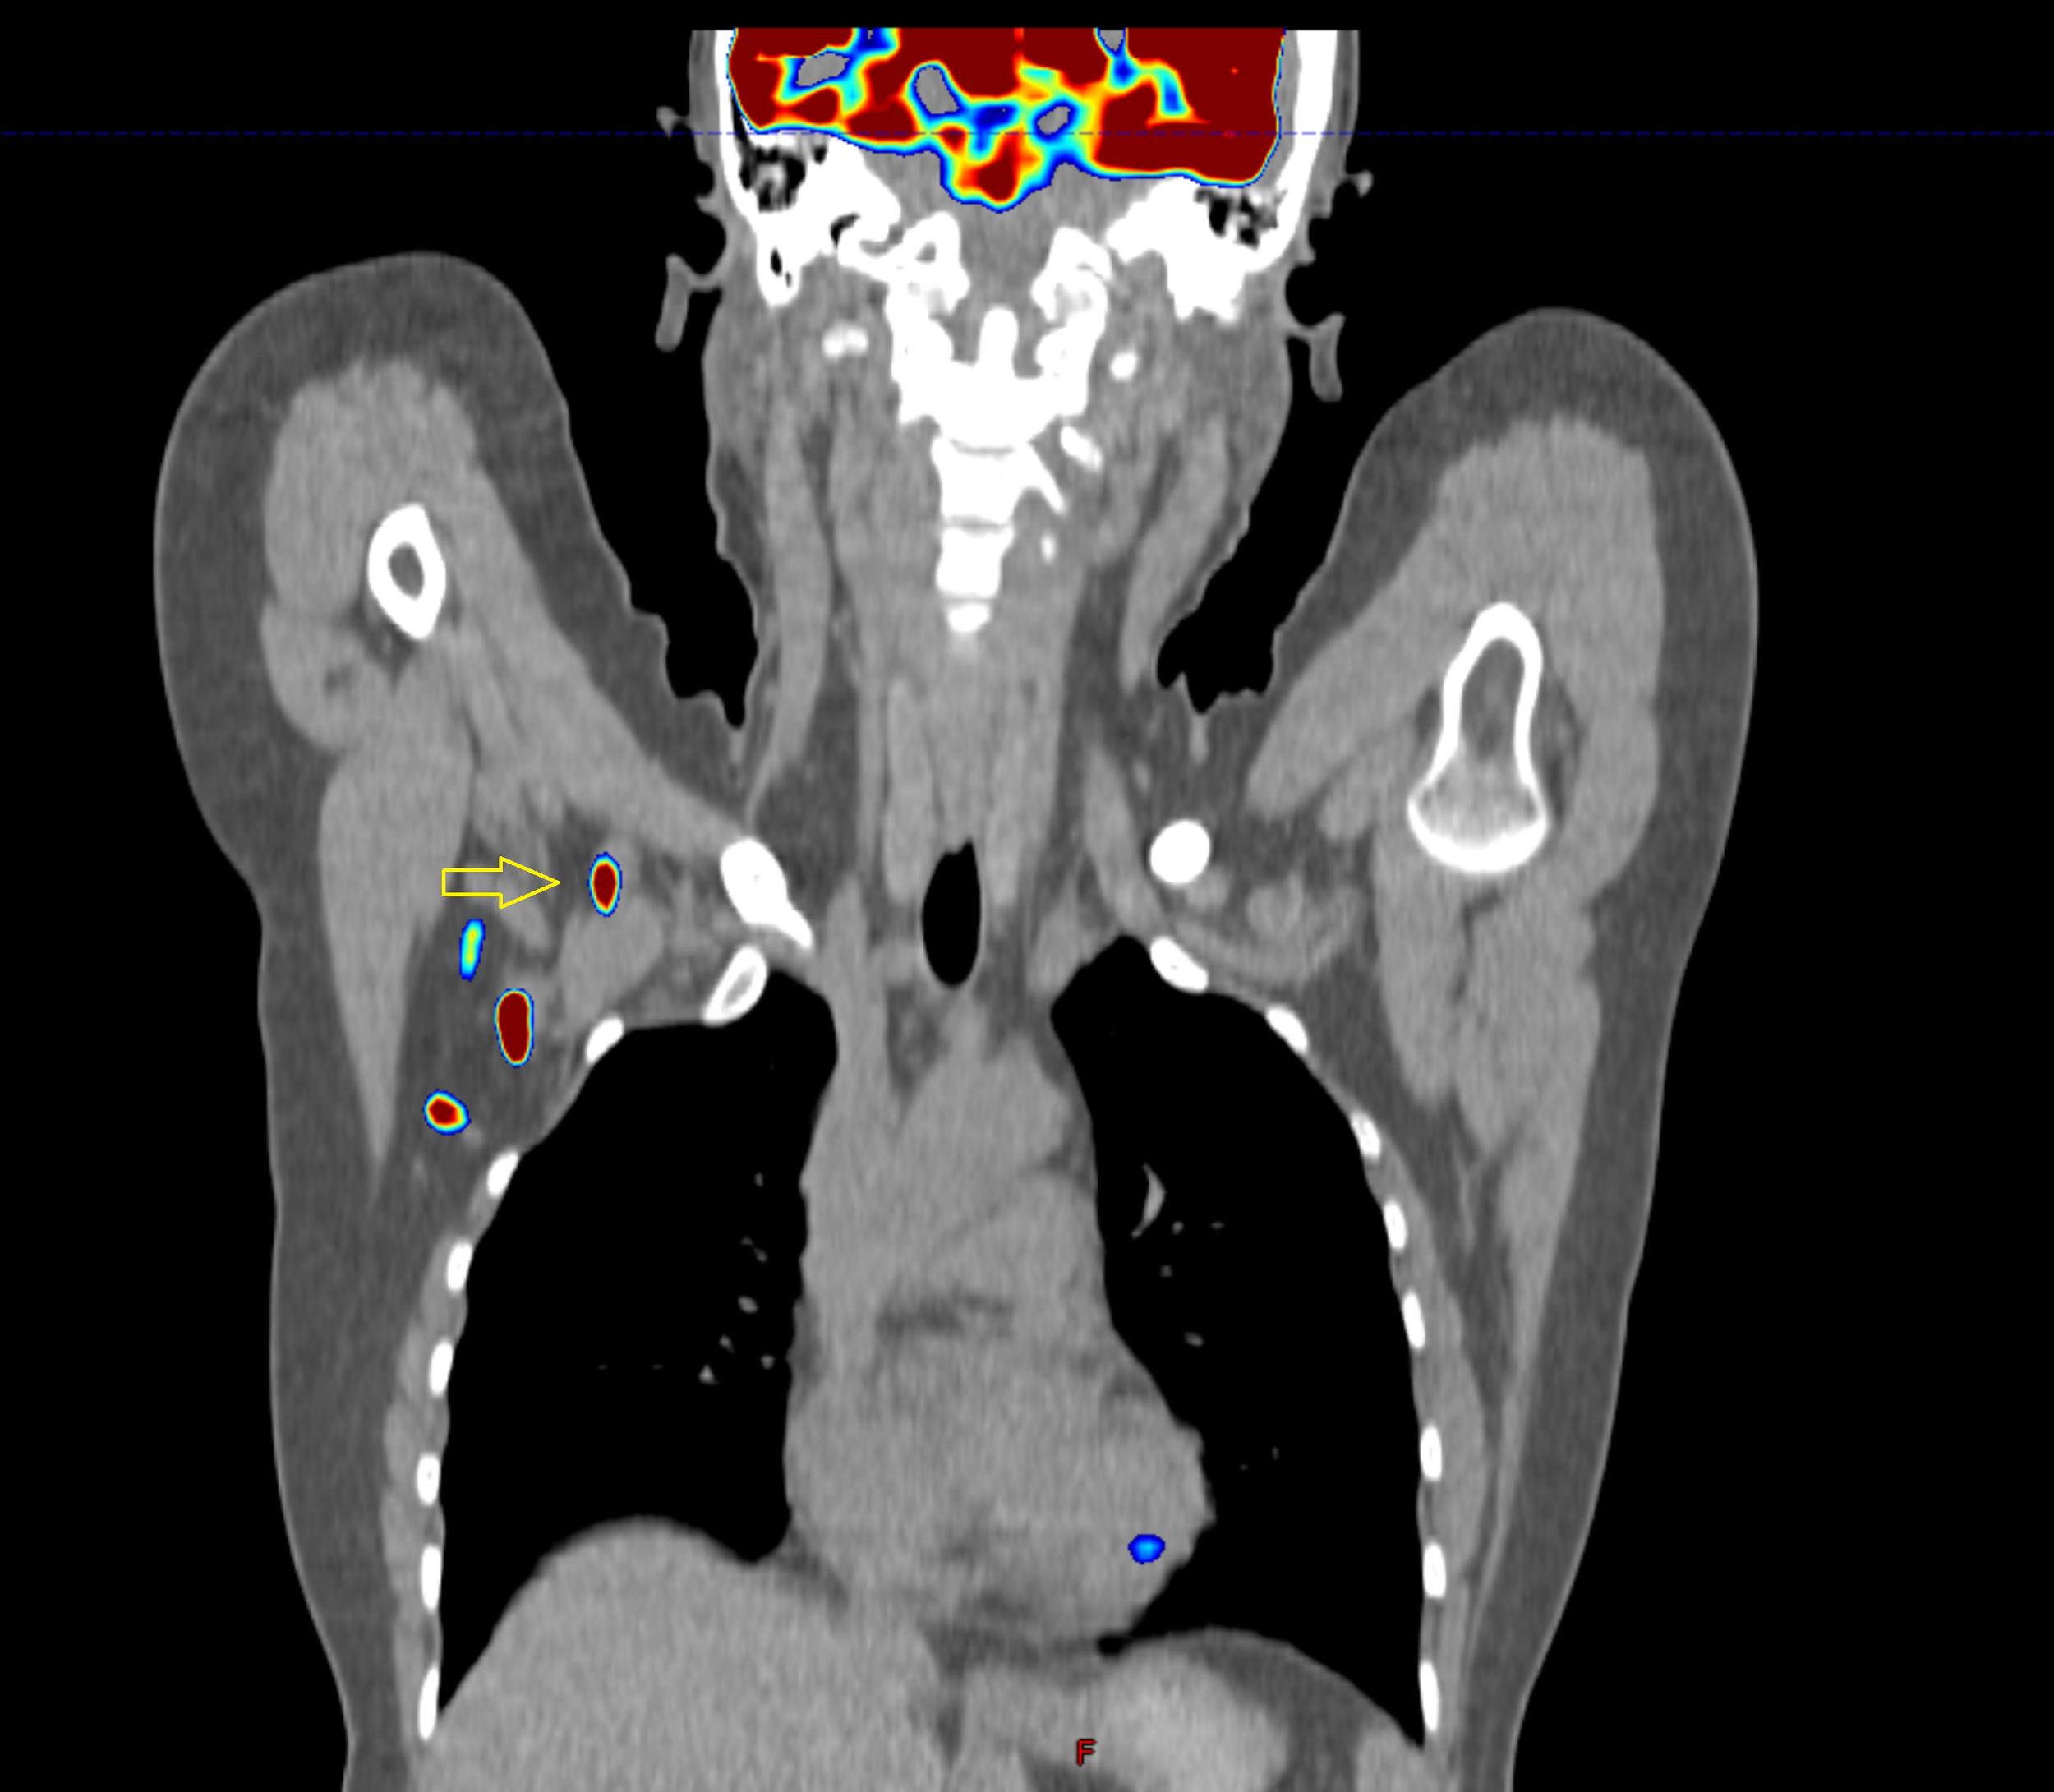

Figure 6

Images of a patient after axillary lymph node dissection, two out of eleven nodes contained metastases. Is this lymph node (yellow arrow) visible on baseline PET-CT operable? What has happened to the third node? It is very likely that it remained in the axilla, despite the surgeon’s efforts.